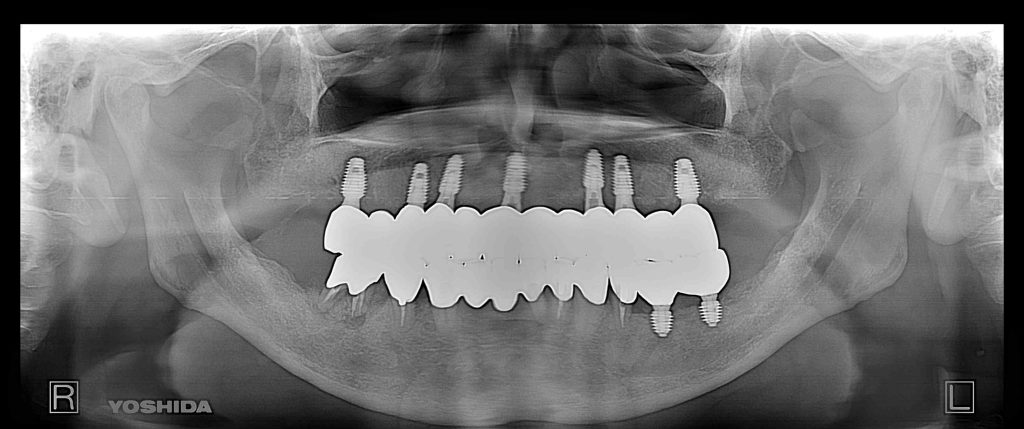

症例550代 男性 主訴 奥歯がグラグラで噛めない

治療前

治療後

しっかり噛めるようになりたい、入れ歯だけは絶対に避けたいと強い訴えがあり、固定制のインプラントを提案。上顎7本、下顎2本、口腔内全体で9本インプラントを埋入。

免荷期間中は、QOLを損なわない為に、暫間インプラント(即時荷重)を埋入、オペ当日に仮歯を装着し、咀嚼可能にした。上顎はAGC(Auro Galvano Conuscrown)ジルコニアブリッジを装着。

治療期間は約5ヶ月間を要した。

リスクとしては外科的侵襲がある。デメリットは、保険外診療の為、経済的負担がある。

費用 628万(税込)(オペ・仮歯・最終補綴物まで含む)